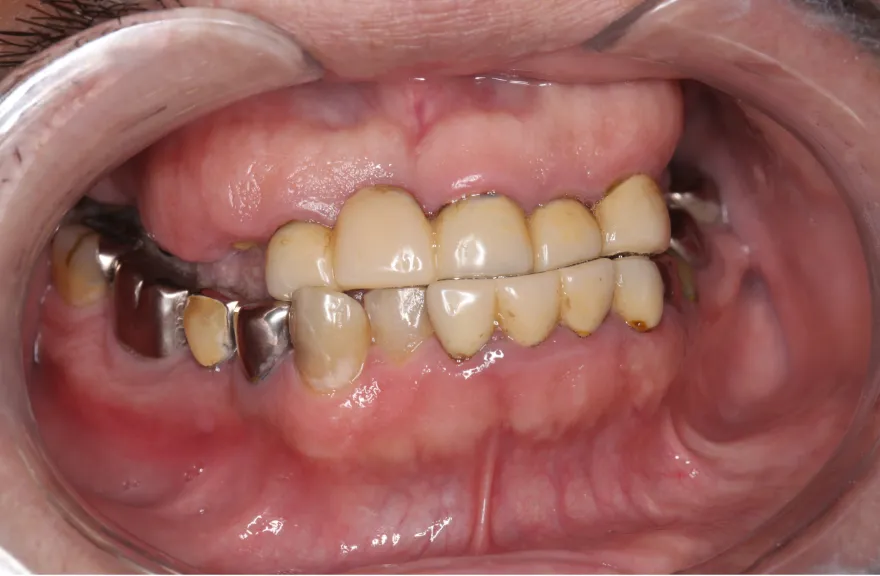

写真の通りに治療を終了いたしました。

上顎は総義歯の形態に、下顎は十分な寿命を持った歯は残して、長期的な保存が難しい歯はインプラント治療を施しました。上顎を総義歯形態にすることにより、何かが起こっても義歯の修理を行えば対応が可能です。即日の修理・完了も難しくないでしょう。

下顎は十分な寿命を持った歯しか残していないので、今後の人生でよっぽどのことがない限りトラブルが起きないと考えます。インプラント治療を施してある部分も、同様にトラブルが起きにくいと考えています。歯周病になった、とか歯が欠けた、というインプラント治療の悪い面が聞こえてくるようになりましたが、噛み合う上の歯を総義歯とすることで、過大な力がかかることなく、トラブルが起きにくい結果を得ることができました。

上顎は総義歯ですが、『今まで食べられなかったものがなんでも噛めるようになった』と、患者さんよりお言葉を頂戴しております。